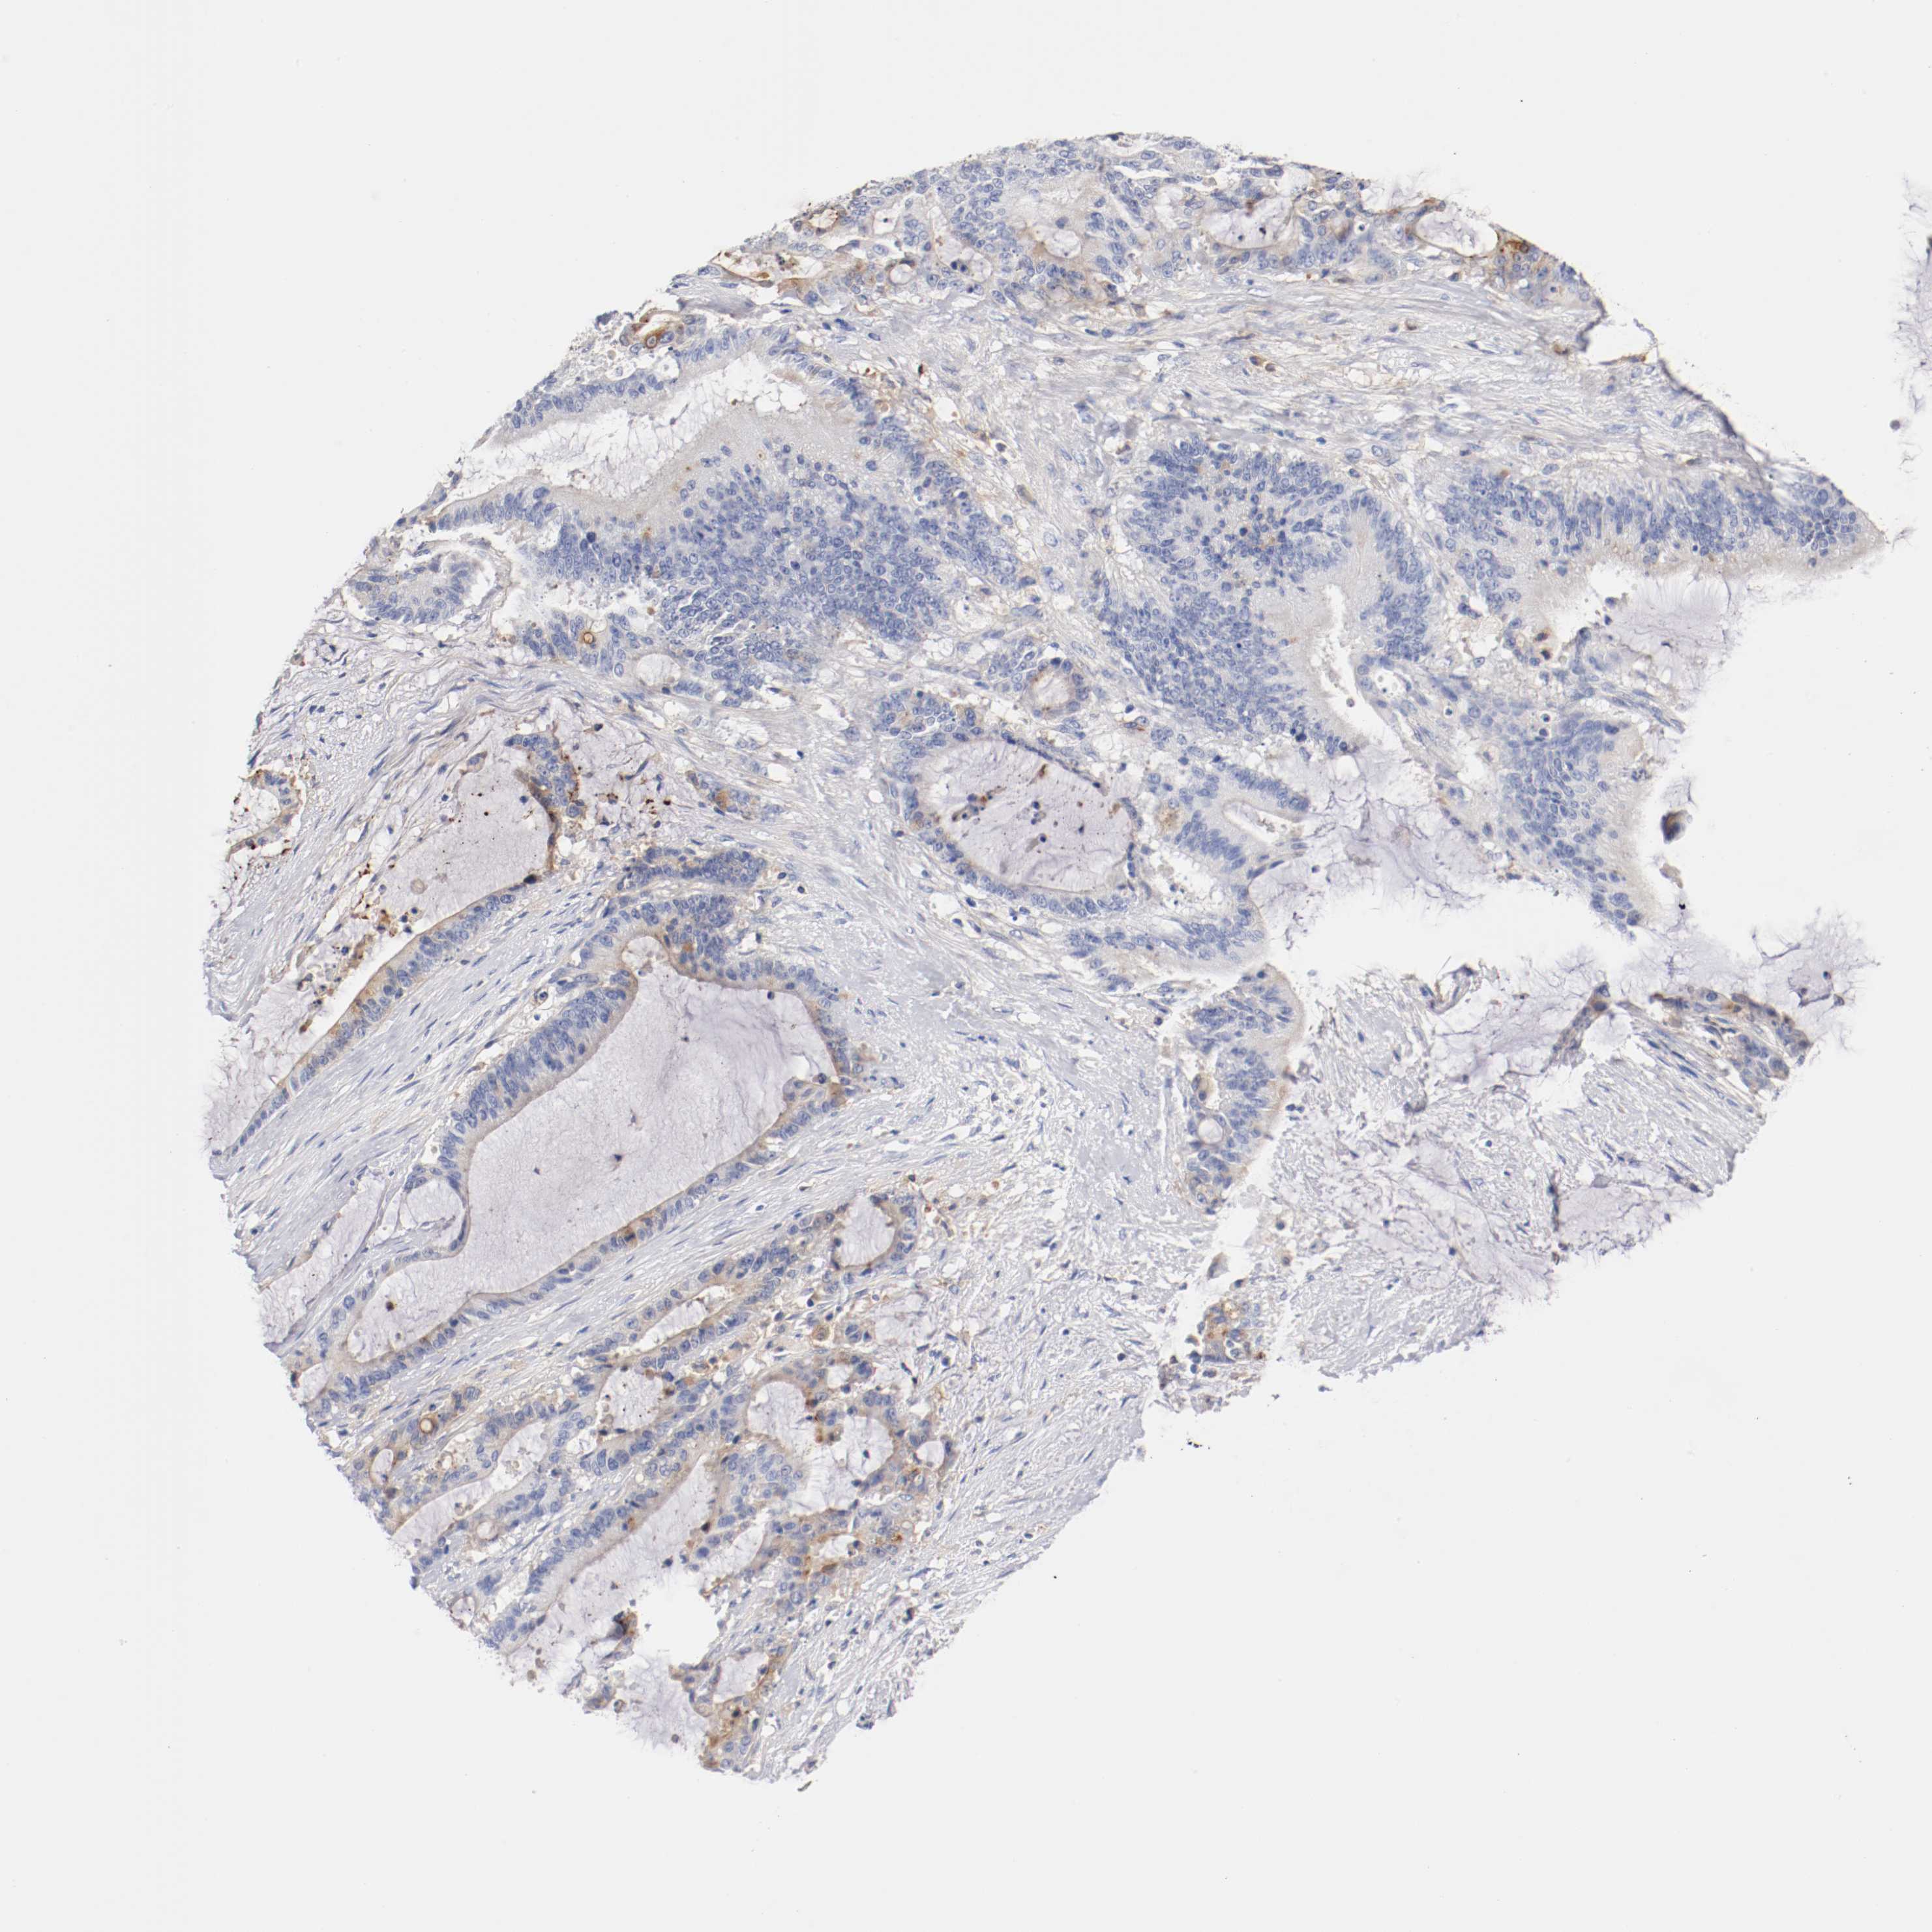

LIVER CANCER - Protein expressioni

A mouse-over function shows sample information and annotation data. Click on an image to view it in a full screen mode. Samples can be filtered based on level of antibody staining by selecting one or several of the following categories: high, medium, low and not detected. The assay and annotation is described here.

Note that samples used for immunohistochemistry by the Human Protein Atlas do not correspond to samples in the TCGA dataset.

Antibody stainingi

Antibody staining in the annotated cell types in the current human tissue is reported as not detected, low, medium, or high, based on conventional immunohistochemistry profiling in selected tissues. This score is based on the combination of the staining intensity and fraction of stained cells.

Each image is clickable and will lead to virtual microscopy that enables deeper exploration of all samples and also displays staining intensity scores, fraction scores and subcellular localization as well as patient and tissue information for each sample.

Antibody HPA004332

Staining

High

Medium

Low

Not detected

Intensity

Strong

Moderate

Weak

Negative

Quantity

>75%

75%-25%

<25%

None

Location

Nuclear

Cytoplasmic/membranous

Cytoplasmic/membranous,nuclear

Cholangiocarcinoma

Carcinoma, Hepatocellular, NOS